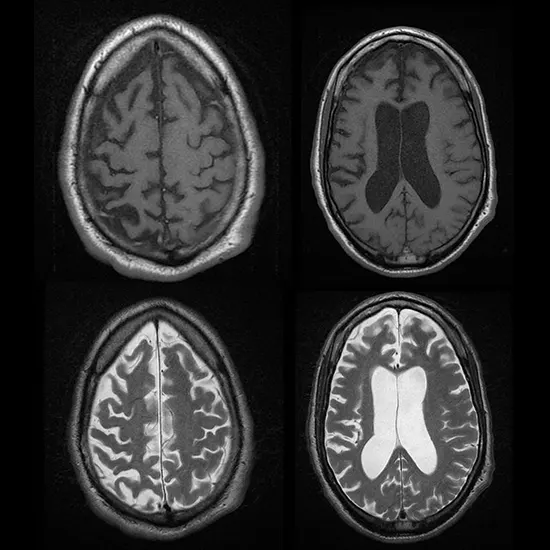

Diagnosis of GSS is typically based on clinical symptoms, family history, and genetic testing to identify mutations in the PRNP gene. Brain imaging studies, such as magnetic resonance imaging (MRI), may also be used to evaluate the brain for characteristic changes seen in prion diseases.

MRI Brain with contrast 11500 5750